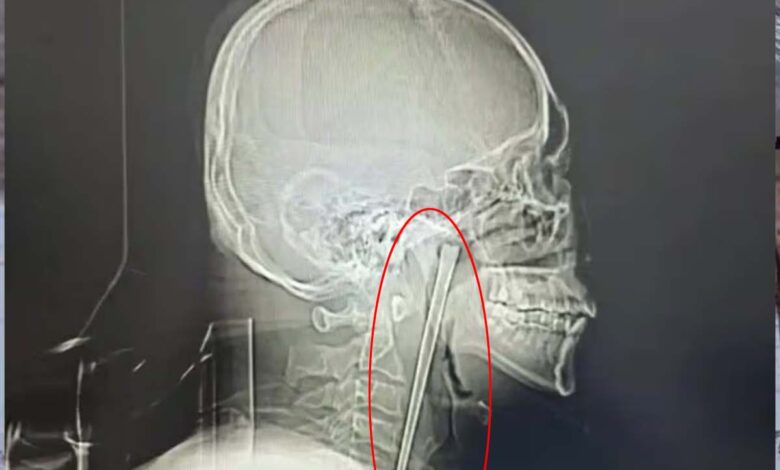

குழந்தைகள் கூட கவனமாக சாப்பிடுவார்களே! என்று நமக்கு நிச்சயம் கேள்வி எழும். குறித்த நபர் மது அருந்திக்கொண்டே நூடுல்ஸ் சாப்பிட்டுள்ளார். அவர் நூடுல்ஸ் சாப்பிடுவதற்கு 12 செ.மீ நீளமுள்ள மெட்டல் சாப்ஸ் ஸ்டிக்கை பயன்படுத்தியுள்ளார்.

திடீரென குச்சியை விழுங்கிய நிலையில், அவை தொண்டையில் சிக்கியுள்ளது. அதனை கழுத்தில் அறுவை சிகிச்சை செய்து எடுக்க வேண்டும் என மருத்துவர்கள் கூறியுள்ளனர்.

இதனால் பயந்து போன குறித்த நபர் 8 ஆண்டுகளாக அப்படியே தொண்டியில் சாப்ஸ் ஸ்டிக்கை வைத்து வாழ்ந்துள்ளார். ஆனால் சமீப காலமாக அதிகமான வலி ஏற்பட்டுள்ளது.

இதனால் மருத்துவமனைக்கு சென்றவர் அங்கு மருத்துவம் மூலம் அறுவை சிகிச்சை செய்து குறித்த சாப்ஸ் ஸ்டிக்கை வெற்றிகரமாக அகற்றியுள்ளனர்.